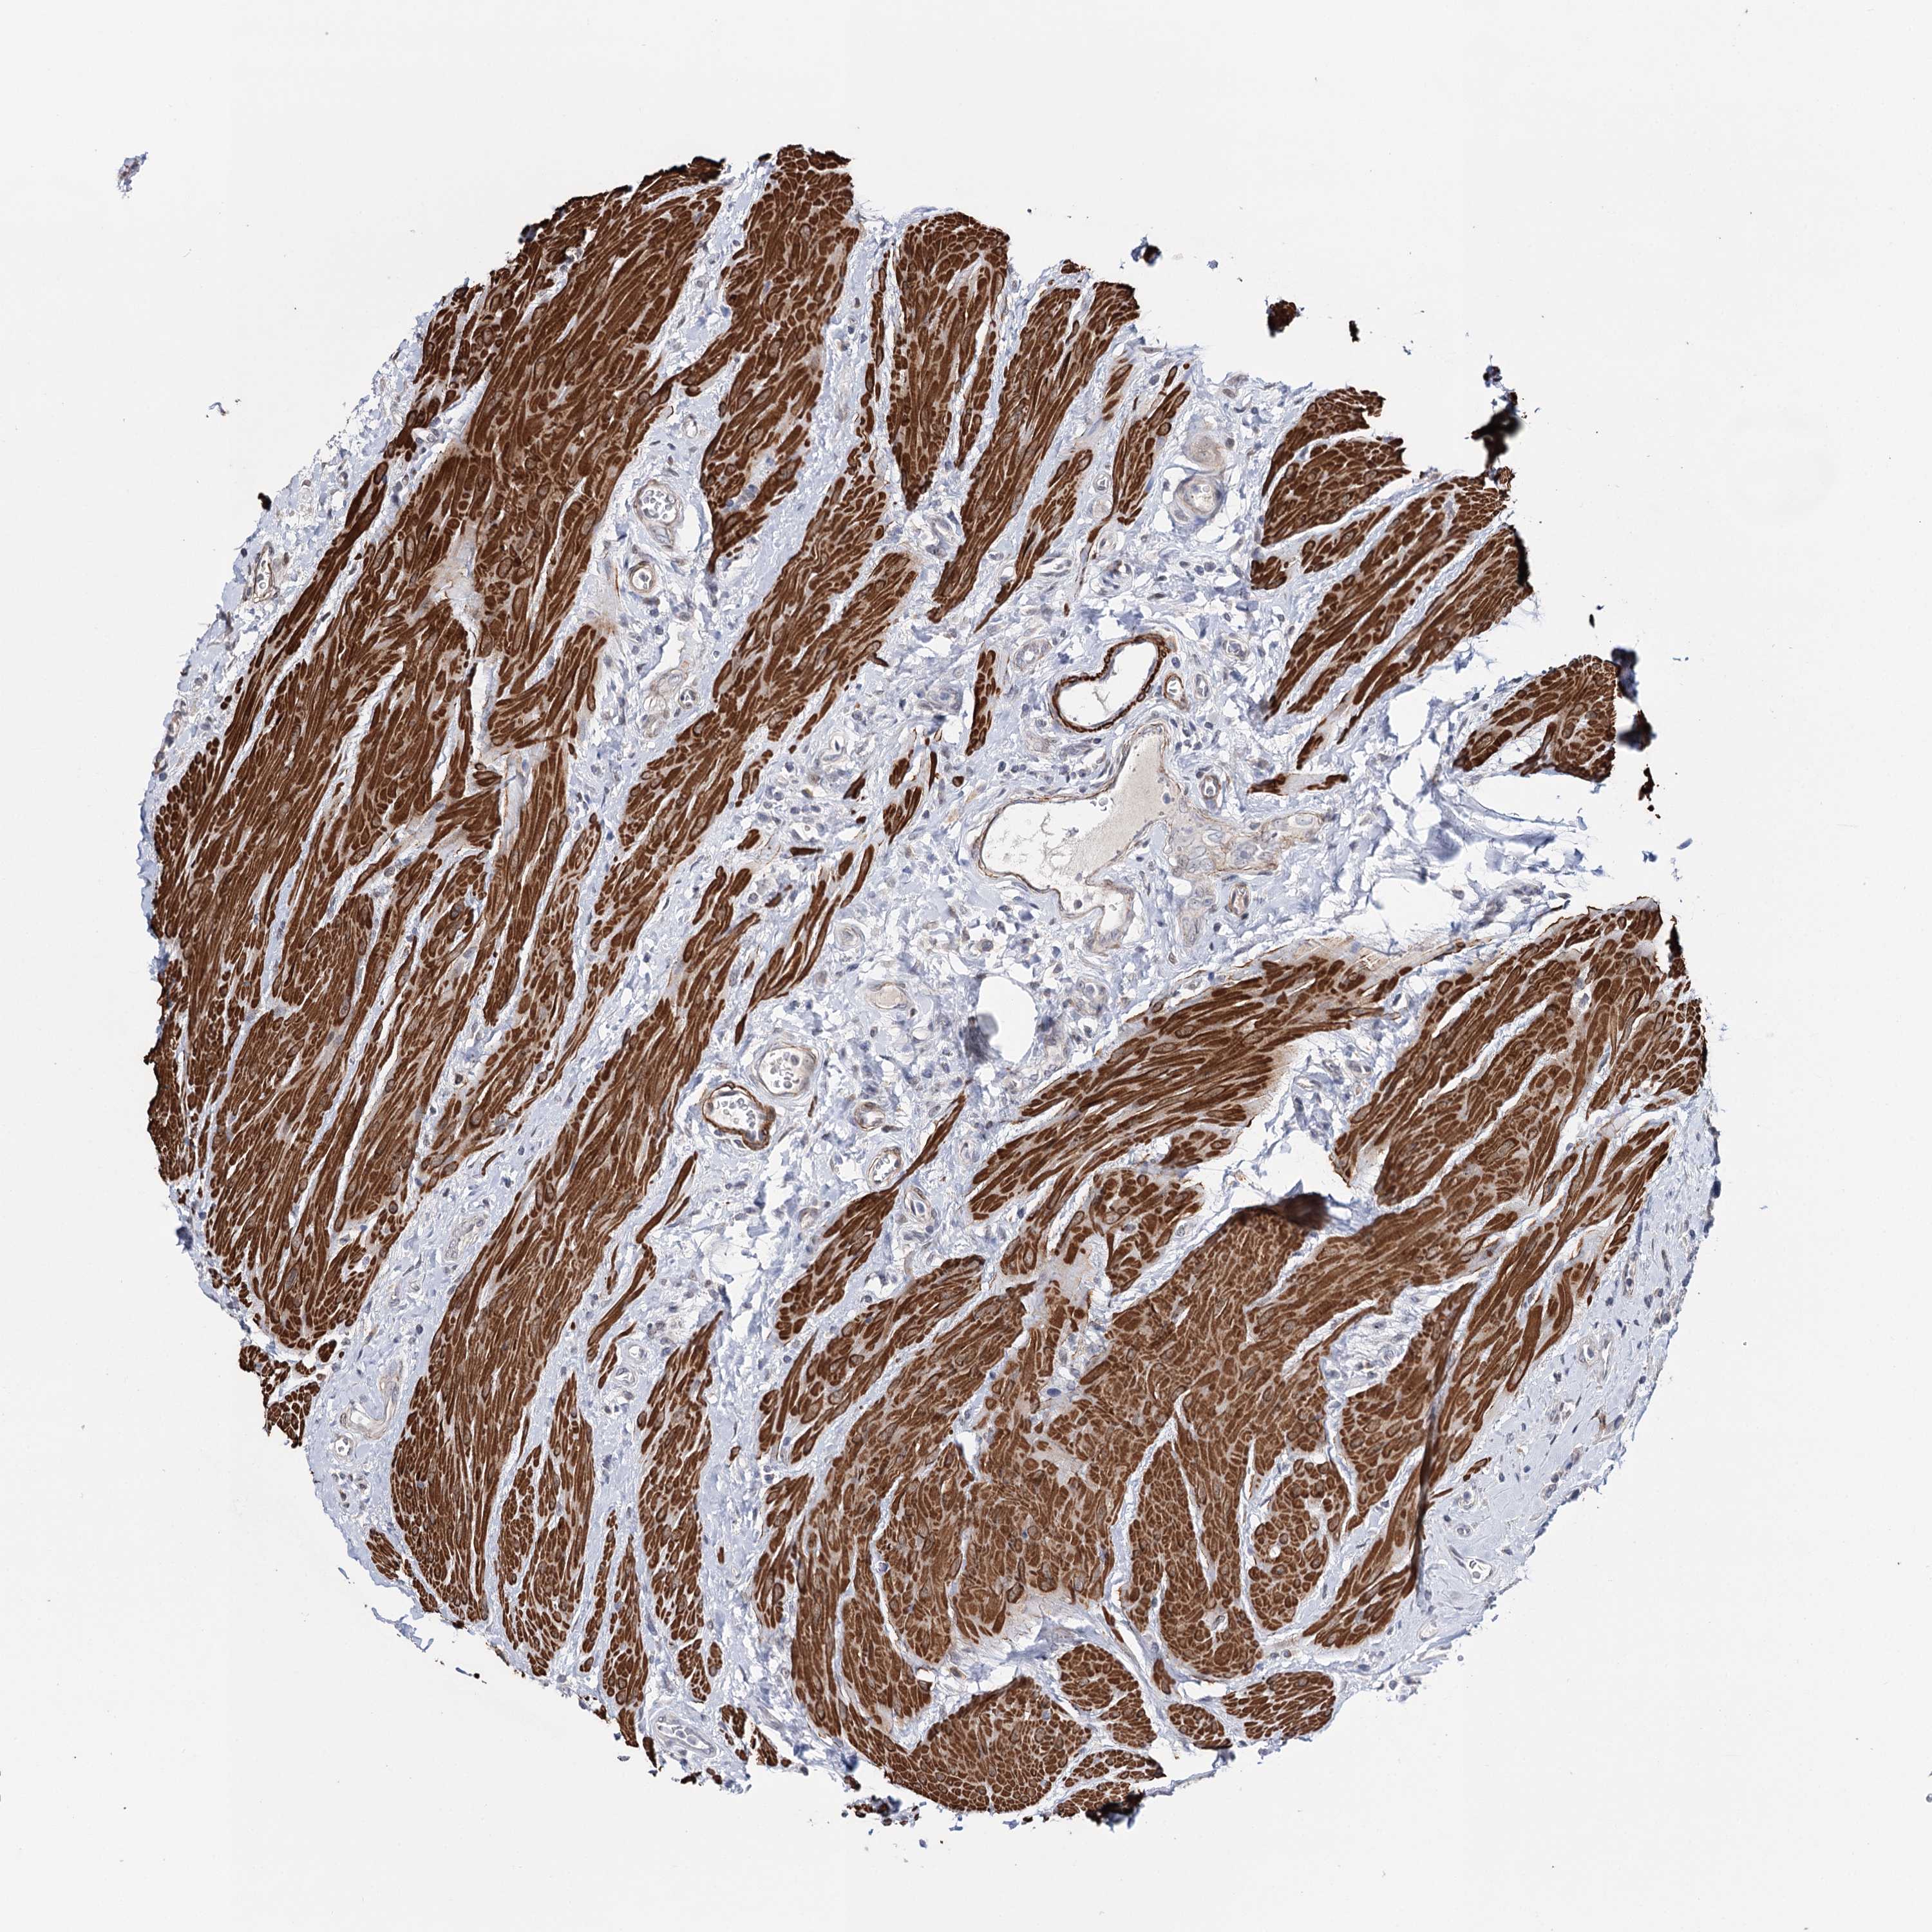

UROTHELIAL CANCER - Protein expressioni

A mouse-over function shows sample information and annotation data. Click on an image to view it in a full screen mode. Samples can be filtered based on level of antibody staining by selecting one or several of the following categories: high, medium, low and not detected. The assay and annotation is described here.

Note that samples used for immunohistochemistry by the Human Protein Atlas do not correspond to samples in the TCGA dataset.

Antibody stainingi

Antibody staining in the annotated cell types in the current human tissue is reported as not detected, low, medium, or high, based on conventional immunohistochemistry profiling in selected tissues. This score is based on the combination of the staining intensity and fraction of stained cells.

Each image is clickable and will lead to virtual microscopy that enables deeper exploration of all samples and also displays staining intensity scores, fraction scores and subcellular localization as well as patient and tissue information for each sample.

Antibody HPA037786

Antibody HPA038034

Antibody HPA038867

Antibody HPA038868

Staining

High

Medium

Low

Not detected

Intensity

Strong

Moderate

Weak

Negative

Quantity

>75%

75%-25%

<25%

None

Location

Nuclear

Cytoplasmic/membranous

Cytoplasmic/membranous,nuclear

Urothelial carcinoma, High grade

Urothelial carcinoma, Low grade

Urothelial carcinoma, NOS